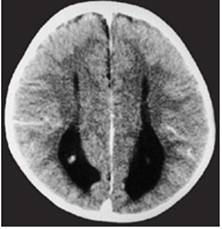

Figure 4

Clinical and image aspects of patient 4